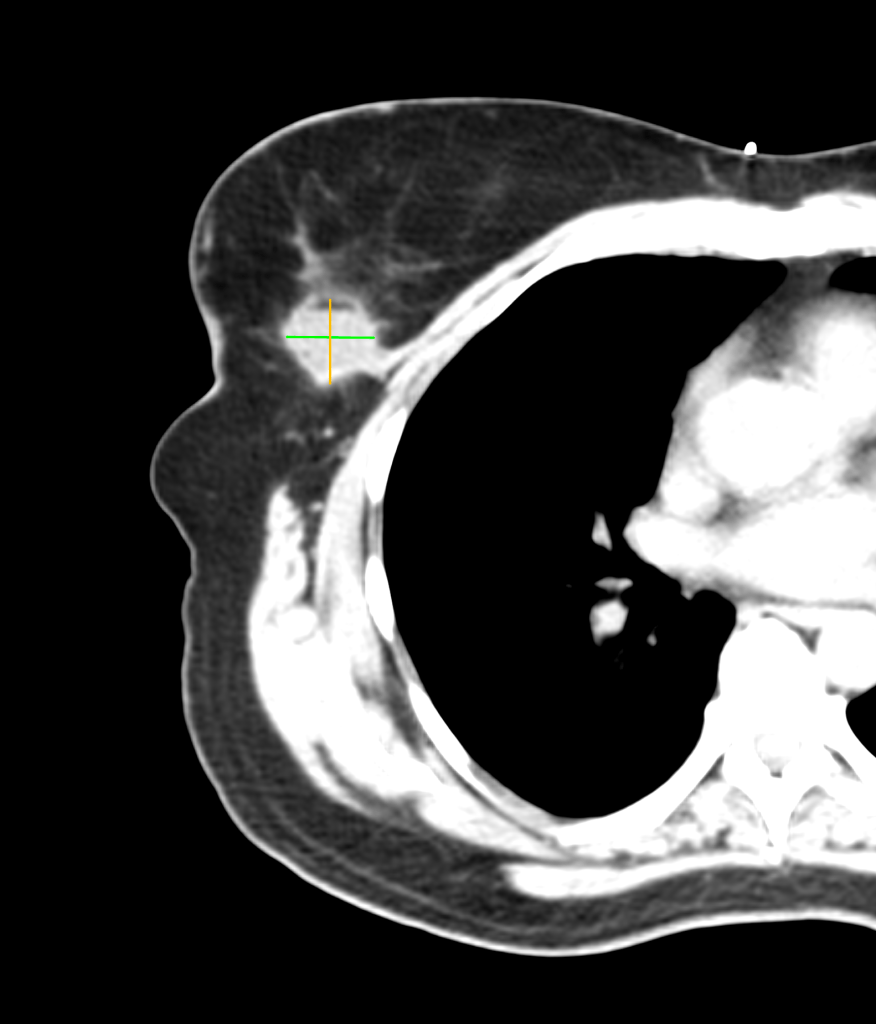

We left Frank’s office and developed a treatment plan with Kimberly’s surgeon and medical oncologist a few days later. The plan included surgery (lumpectomy) followed by radiation therapy. Surgery was successful, as you can see in the before and after images below. (Special thanks to the Horos Project for the open source DICOM viewer.)

Before surgery

After surgery